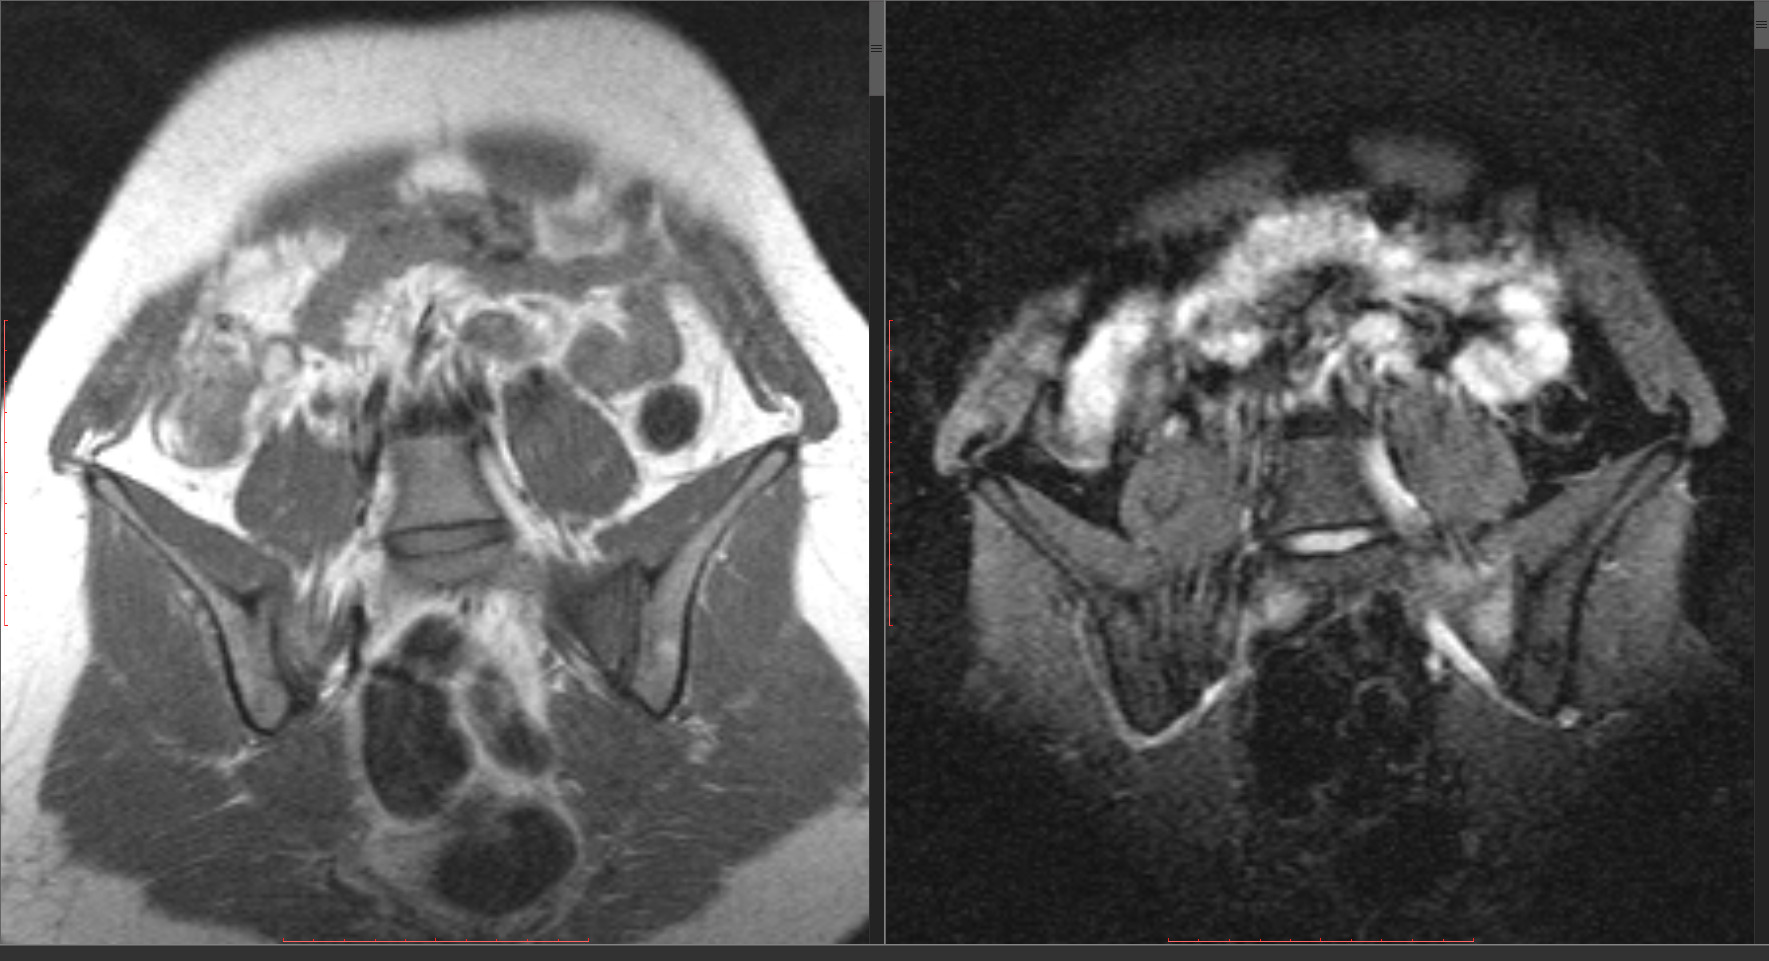

vadim losevichev wrote:

Это?

Видимо да, тут лучше видно

Потому что линия не "сквозная" (не разделяет боковую массу на 2 части), нет травмы в анамнезе,а месяц назад начала интенсивно заниматься аэробикой.

Всё-таки не нужно стрессом все переломы теперь величать. Тем паче, что на 7 слайде есть линия, выходящая за кортикал. Перелом случается и не делит на части, а только трещиной ограничивается - кость целая, болит, но функционирует, а перелом в ней лежит и только на снимках себя проецирует.)